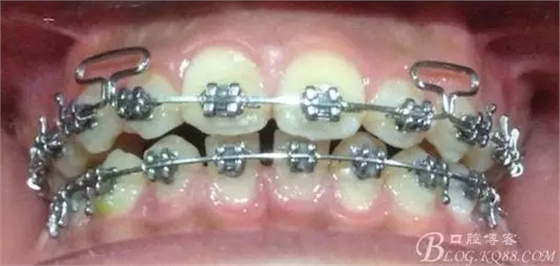

看看口內(nèi)照吧!真象“大暴牙”v假象“大暴牙”

640.webp.jpg

三度深覆合,三度深覆蓋,尖牙,磨牙均二類關(guān)系!